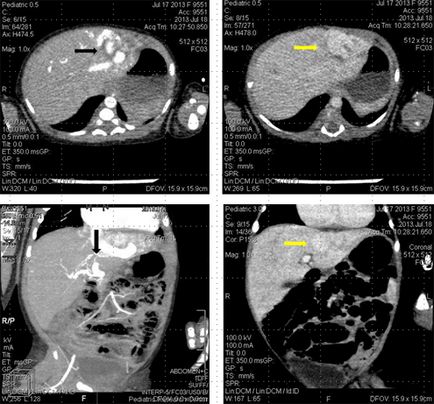

Pentru a identifica fistulei arteriovenoase și leziuni maligne ale lobului stâng al ficatului este prezentat studiul CT cu contrast intravenos accesoriu.

La CT, la vârsta primei zile de viață, o anomalie vasculară congenitală a ficatului a fost identificată ca un hemangiom infantil.

A fost detectată o șuntură arterio-venoasă între ramura arterei hepatice comune și vena cavă inferioară.